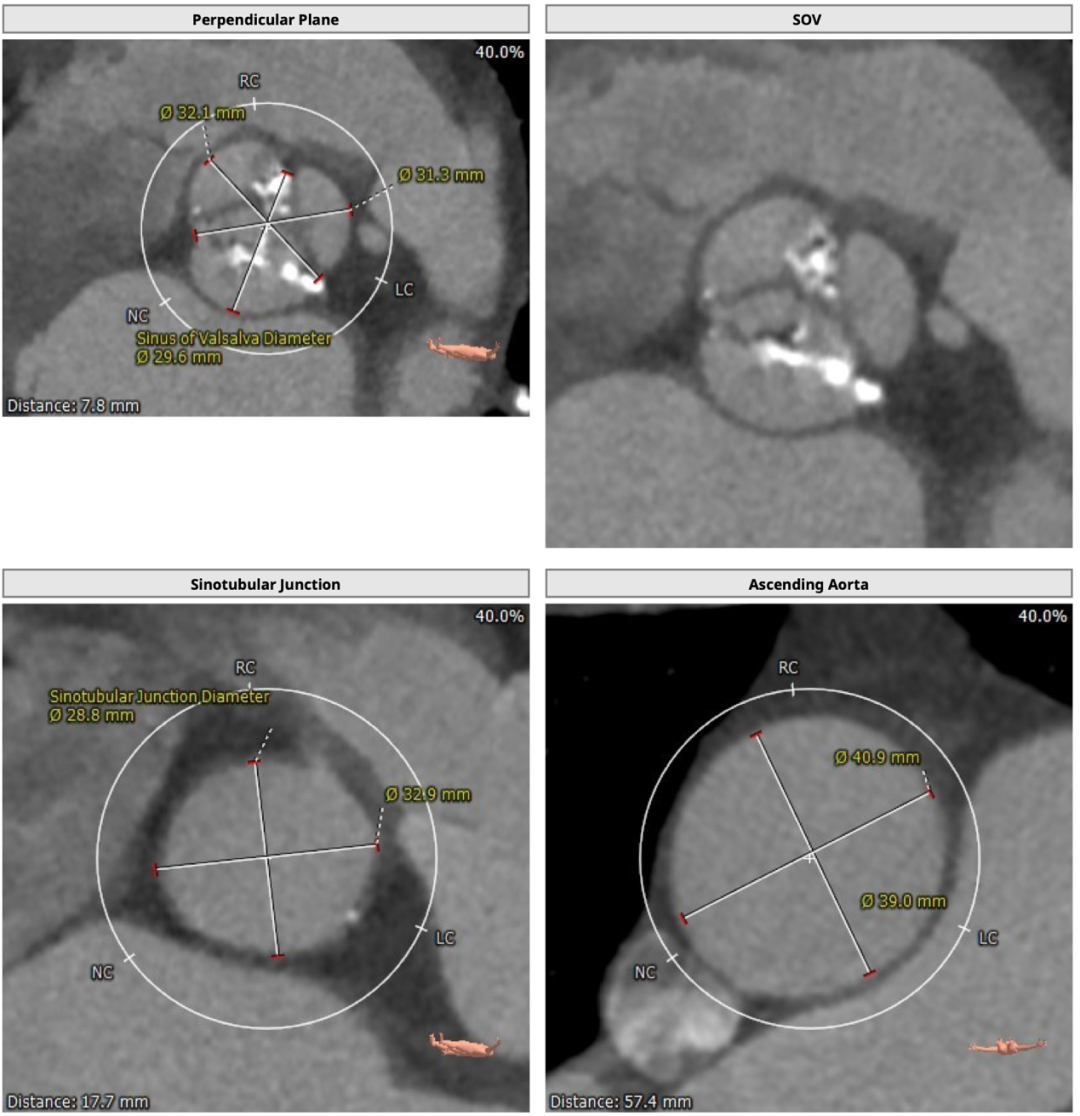

术前CT

为三叶式主动脉瓣,瓣叶钙化较重,瓣环周长获得平均直径23.5mm,左右冠脉开口高度分别为11.2和16.4mm。瓣叶冗长,左冠开口水平可见瓣叶,左冠有堵塞风险。双侧股动脉走行流畅,无明显钙化迂曲,左右最细处分别为6.5和6.6mm。